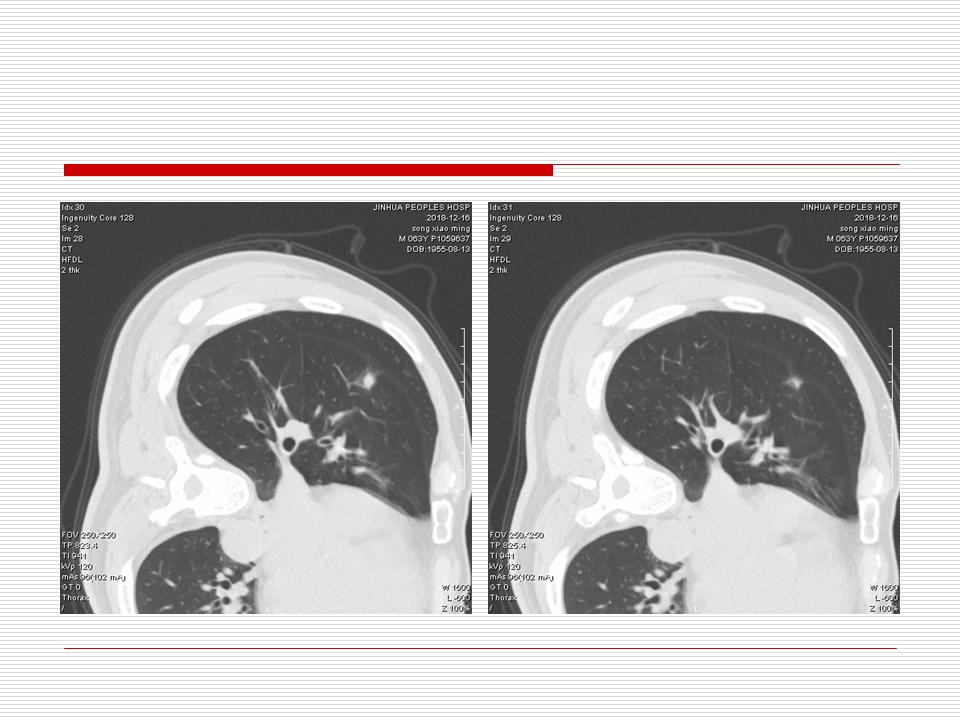

肺部阴影永恒且最重需要鉴别的是:到底是炎症还是肿瘤?但临床的病例中的影像表现难以界定或有些肿瘤特征,同时又有些炎症特点是非常常见的情况。作为临床医生我们怎么去总结分析,并找到之所以是炎症或之所以是肿瘤的细微差别或特点非常重要,也非常有用。2019.12.7浙江省2019年胸心外科学学术年会在宁波召开时,我的临床病例分析与经验总结<那些像肺癌的炎症与像炎症的肺癌>获得在大会交流的机会,以下为该PPT的内容,与你分享,希望对同道有益,有借鉴与启迪。若有探讨与进一不完善的建议,欢迎文末留言讨论: